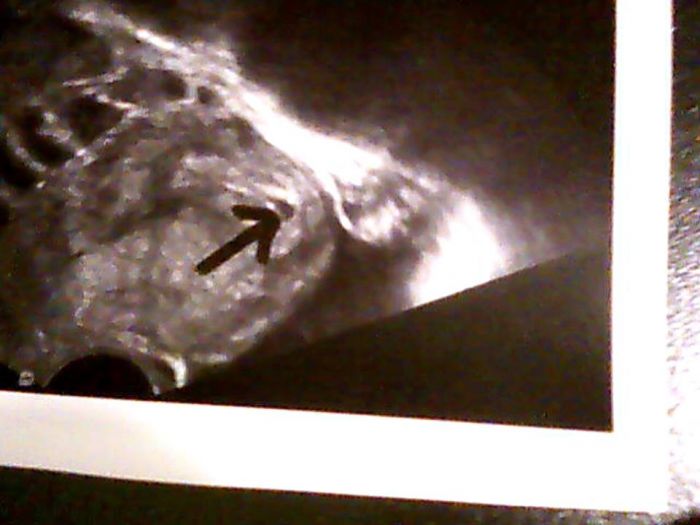

,tak jsem šla za chvíli na wc znova a čárka tam byla,to bylo ve čtvrtek ráno.V sobotu jsem si udělala další test a čárka byla vidět zase o něco lépe,takže jsme letěli v pondělí na gyndu,tam doktorka najela a říká no těhotenství tam je,ale úplně na začátku to byl tak 4 týden a říká za týden na kontrolu,o týden později to jsem byla 5+3 byl už vidět větší gestační váček i se žloutkovým,ale plod ještě vidět nebyl.A ted v pondělí to jsem byla 6+3 už byl vidět jak gestační váček,tak i žloutkový váček a plod se srdíčkem....dám sem všechny tři ultrazvuky at může porovnat jak to rychle roste

a tak ta první to je 4+3 ta druhá vedle ní to je 6+3 a ta spodní v druhém příspěvku je 5+3